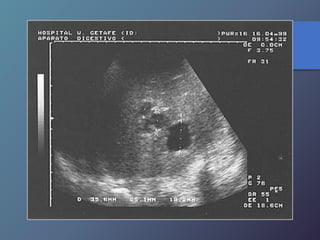

Aneurisma de la Vena Porta

• Son poco frecuentes, generalmente presentan un origen

congénito.

• Sin embargo puede ser adquirido por hipertensión

portal.

• Ecográficamente se observan en los tercios proximales

de las venas mesentérica superior y esplénica.

• Ecográficamente se observa como una masa quística

anecoica que se conecta con e sistema venoso portal.

• Al doppler pulsado muestran flujos venosos turbulentos.